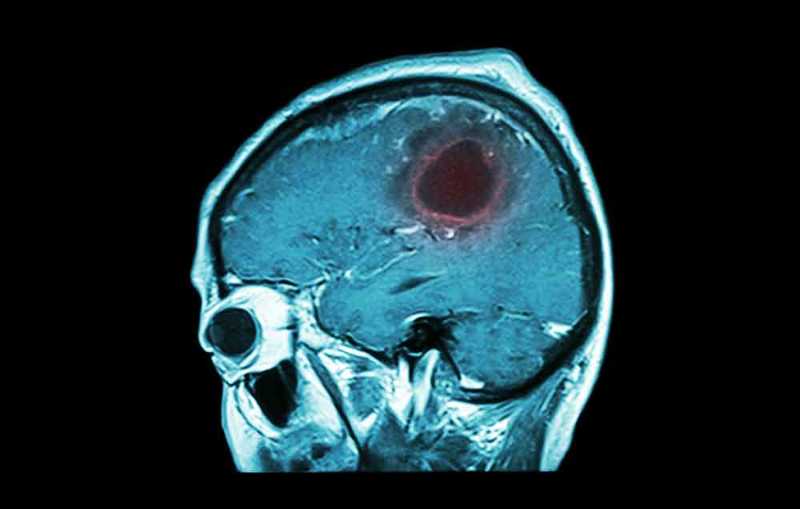

Με τα χρόνια, έχει σημειωθεί αύξηση των περιπτώσεων με όγκο του εγκεφάλου. Μόνο στις ΗΠΑ, εκτιμάται ότι πάνω από 700.000 άνθρωποι αντιμετωπίζουν σε αρχικό στάδιο όγκο στον εγκέφαλο και όγκο στο κεντρικό νευρικό σύστημα του εγκεφάλου.Ο όγκος στον εγκέφαλο εμφανίζεται όταν ένας ιστός στον εγκέφαλο ή στη σπονδυλική στήλη εμφανίζει ανώμαλη ανάπτυξη. Αυτό εμποδίζει τις σωστές λειτουργίες του εγκεφάλου.

Ο όγκος στον εγκέφαλο εμφανίζεται όταν ένας ιστός στον εγκέφαλο ή στη σπονδυλική στήλη εμφανίζει ανώμαλη ανάπτυξη